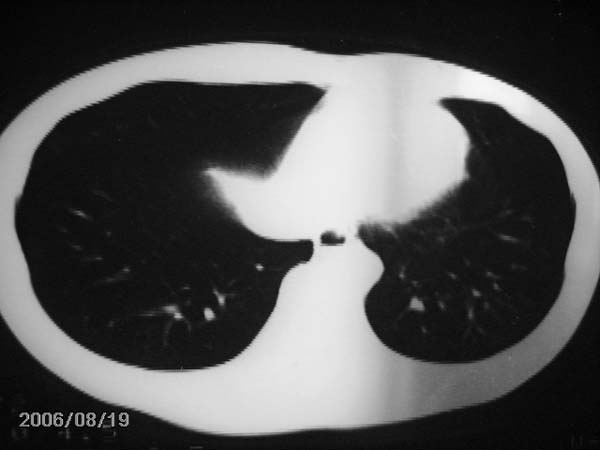

男,13岁,发烧半月,干咳无痰,正规使用抗生素半月,现在仍是午后低烧!!!未做痰检

右肺结核,右肺中叶不张

右肺中叶大片状密度增高影,内密度不均匀,右肺门处增大,应该是淋巴结肿大,结合临床首先考虑原发性肺结合可能性大,不排除合并感染可能,建议治疗后复查.

右肺结核,干酪性肺炎形成

灶内密度不均,似乎有囊状,条状影,考虑右中叶综合症; 从照片中看不出有无钙化灶,若明显则考虑结核性。

肺结核中叶综合征

考虑中叶综合征(右肺门肿大淋巴结伴中叶阻塞性炎症)